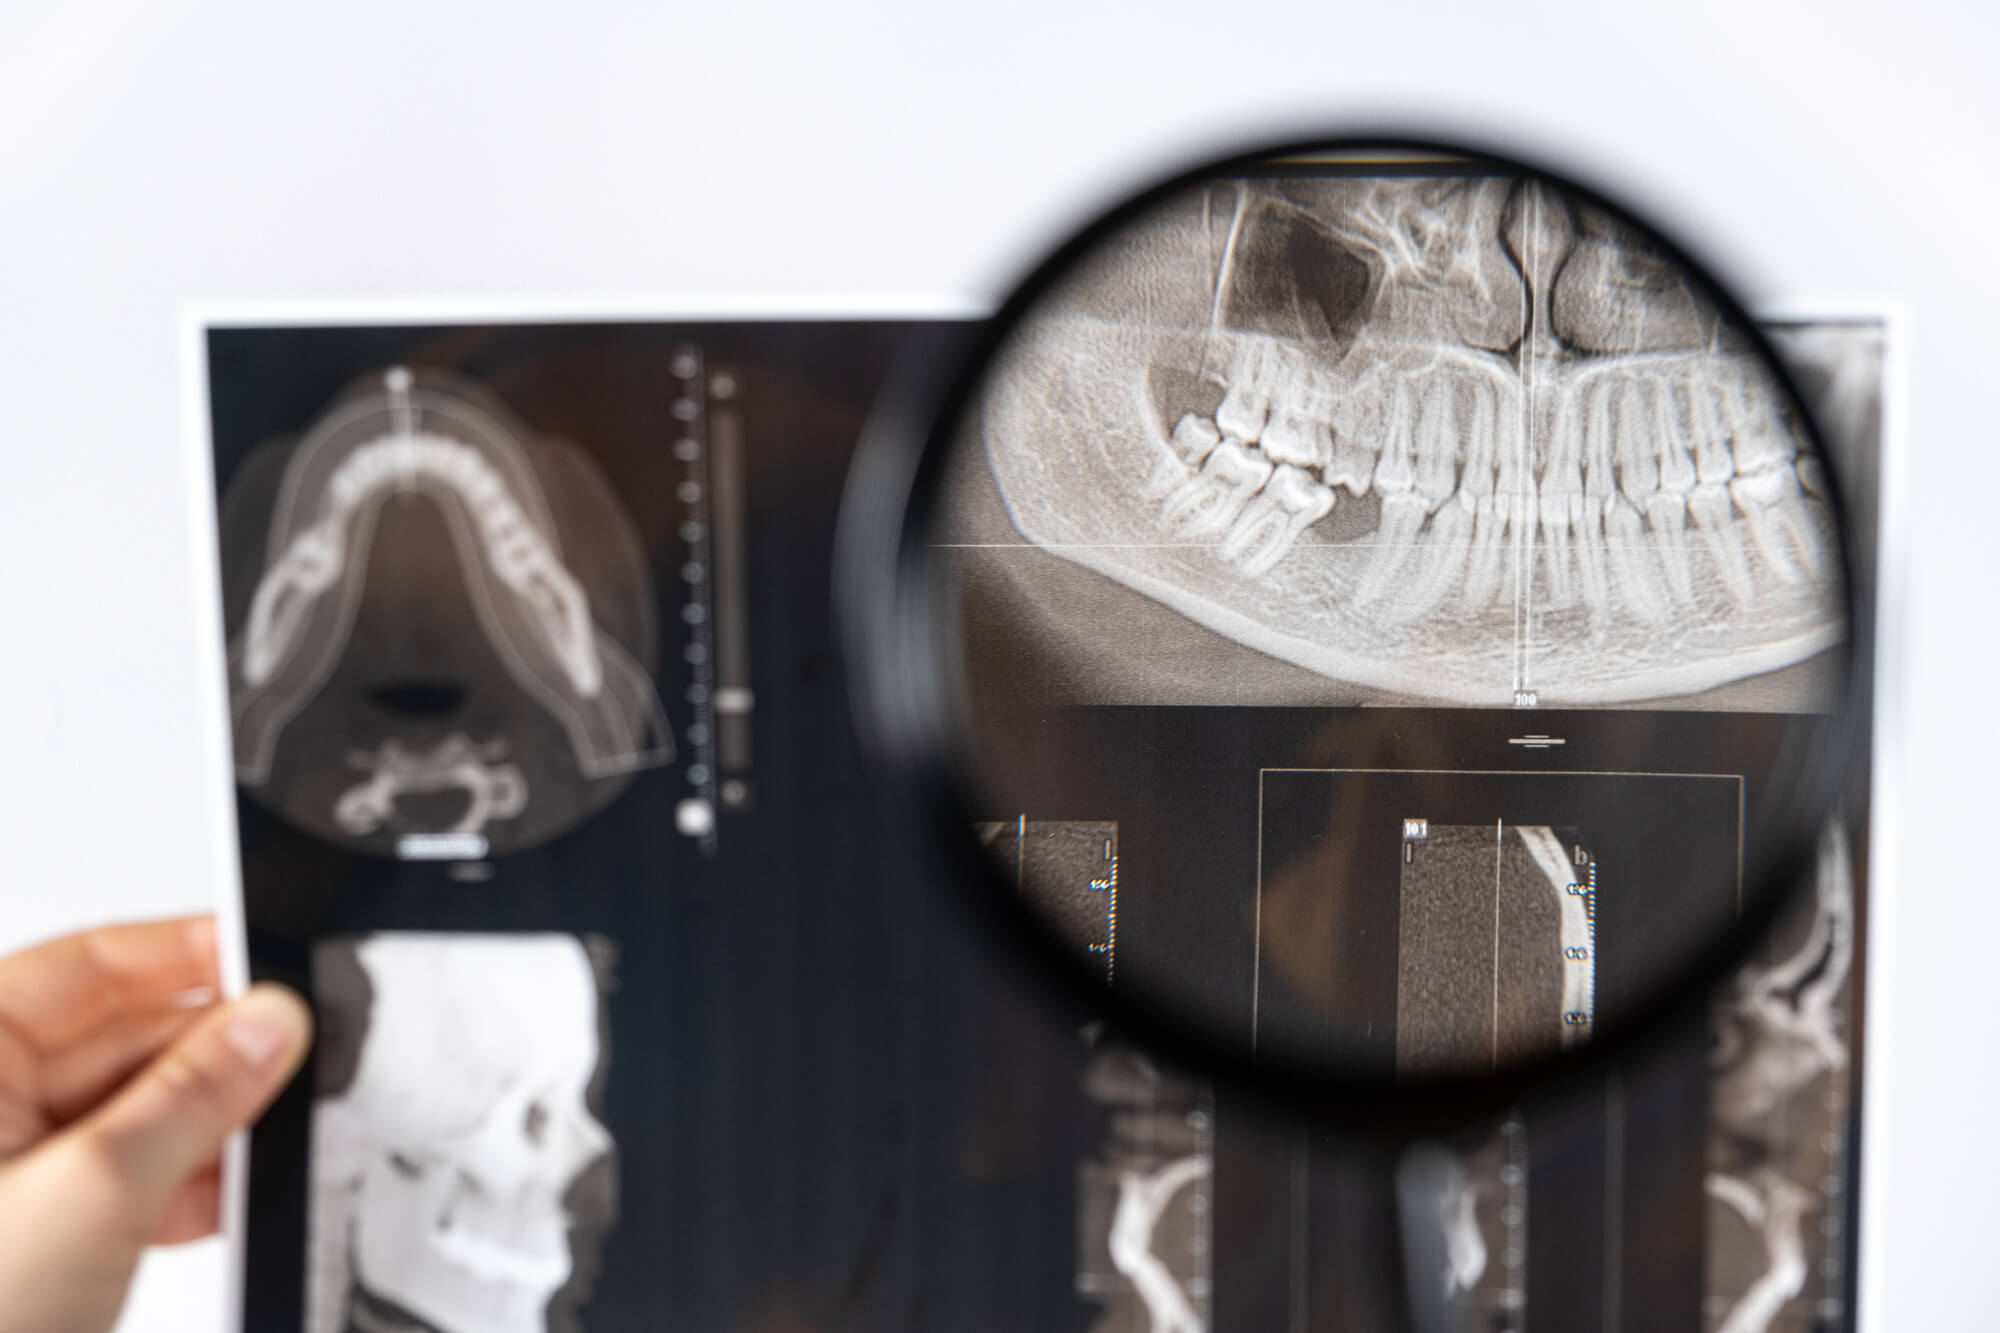

インプラント手術を受ける前には、まず口腔内の状態を詳しく把握するために検査を行います。問診やレントゲン撮影、虫歯や歯周病チェックなどがあり、CT撮影ではインプラントを埋入するために大切な骨の量や質、幅、高さを確認します。

その資料をもとに担当の歯科医師が治療計画を作成し、その診断結果とともにインプラント手術に関する内容やメリット・デメリット、注意点などについて説明されるのが一般的です。

当院では、最新の歯科用CTを導入しているため、骨の厚みや高さ、神経・血管の位置を正確に把握することができます。その精密な診断をもとに、事前に治療計画を立てることで安全で成功率の高い手術を行うことを可能にします。